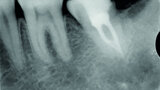

Fig. 3: Pre-op periapical radiograph.